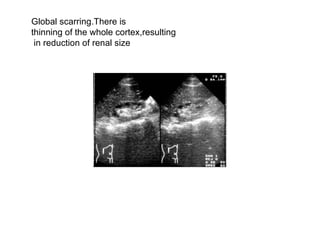

Global scarring.There is  thinning of the whole cortex,resulting in reduction of renal size